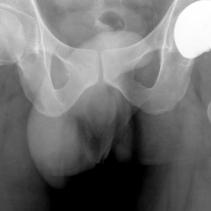

As we get older we tend to take more notice of our body - often it can be too late, we always advise an ounce of prevention rather than a pound of cure. We have a quick test to find out if your hip needs a pound of replacement.